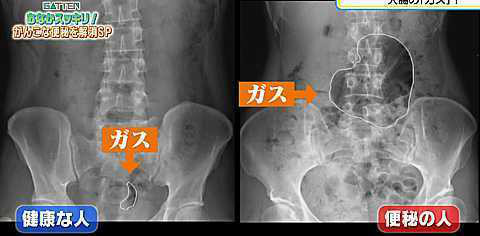

食物繊維や発酵食品など腸に良いといわれている食品、実は過敏性腸症候群の人々にとっては腸の不調を悪化させてしまいます。

過敏性腸症候群の症状は、ある特定の食品群が原因のひとつであることがわかってきました。

例えば、食物繊維が豊富なごぼうやニラ、発酵食品の納豆、ヨーグルト、キムチなど、普通の人には腸を整える素晴らしい食品ですが、過敏性腸症候群の人にとっては腸の不調をさらに悪化させてしまう食品だったのです。